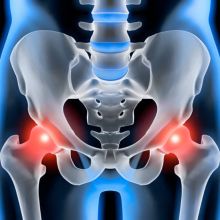

Bolesti kyčelního kloubu